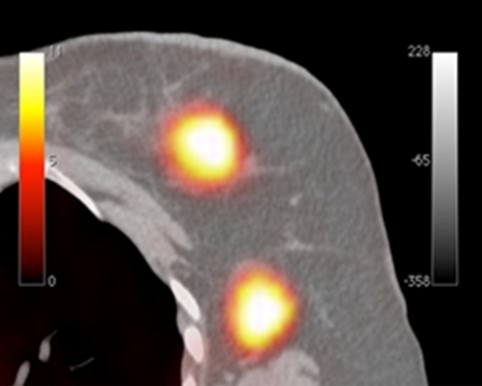

Clear PEM Device Clinical Image

Due to its very good spatial resolution and accessibility of the Field-of-View, the Clear-PEM system can also be used for small animal imaging.